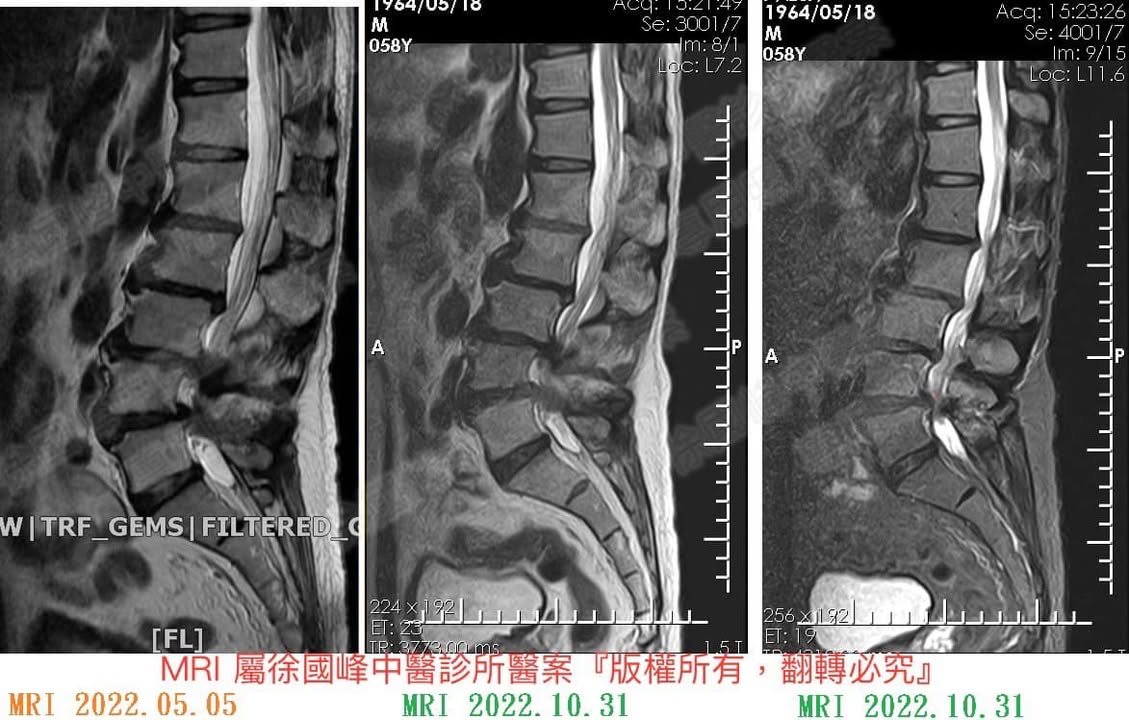

1.L2L3椎體滑脫合併L3L4;L4L5中度椎孔狹窄

4️⃣核磁共振掃描 (MRI) - 核磁共振掃描對於評估脊椎的問題非常有用,因為它能顯示出神經、其他軟組織和骨骼。